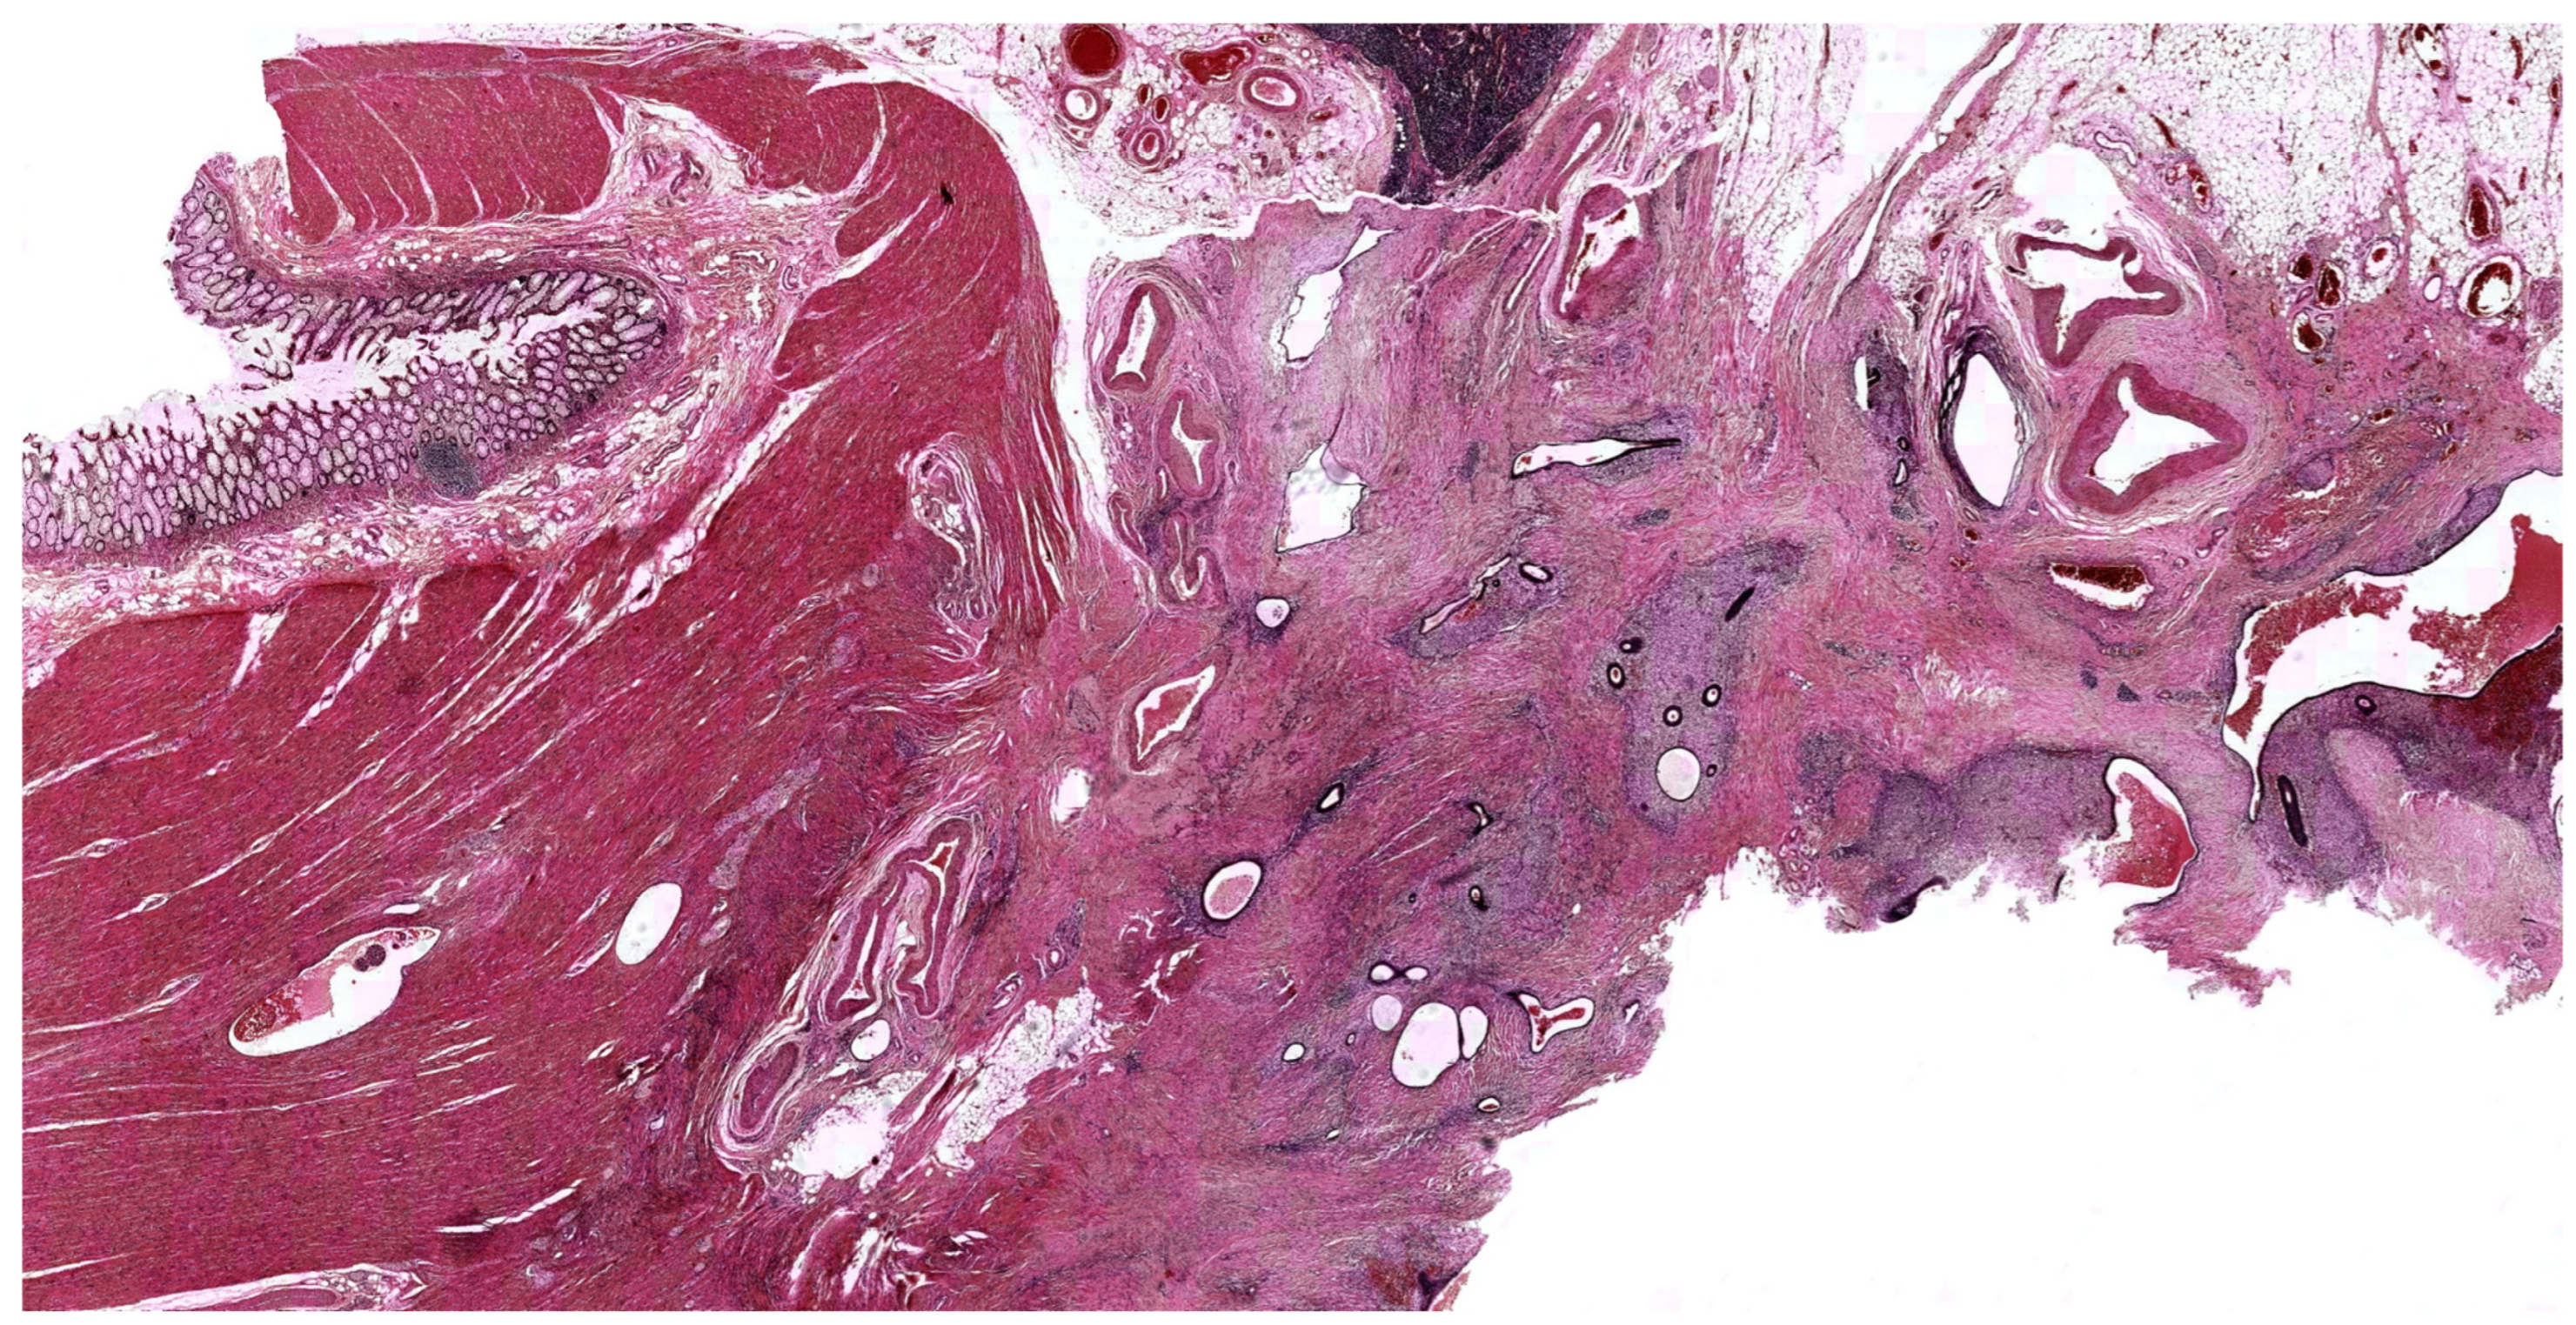

- Guadagno, A.; Grillo, F.; Vellone, V.G.; Ferrero, S.; Fasoli, A.; Fiocca, R.; Mastracci, L. Intestinal endometriosis: Mimicker of inflammatory bowel disease? Digestion 2015, 92, 14–21. [Google Scholar] [CrossRef]

- Fenoglio-Preiser, C.M. Gastrointestinal Pathology: An Atlas and Text, 3rd ed.; Wolters Kluwer/Lippincott Williams & Wilkins: Philadelphia, PA, USA, 2008; pp. 878–881. [Google Scholar]